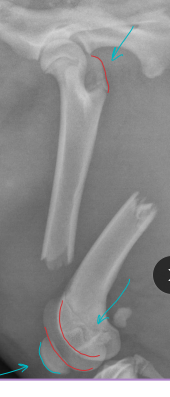

Distal Physeal fractures: young, Salter-Harris type, growth plate involvement

Tx: cross pins (linear), plates (if comminuted)

Risk of quadriceps contracture(esp. extended postion) peg leg